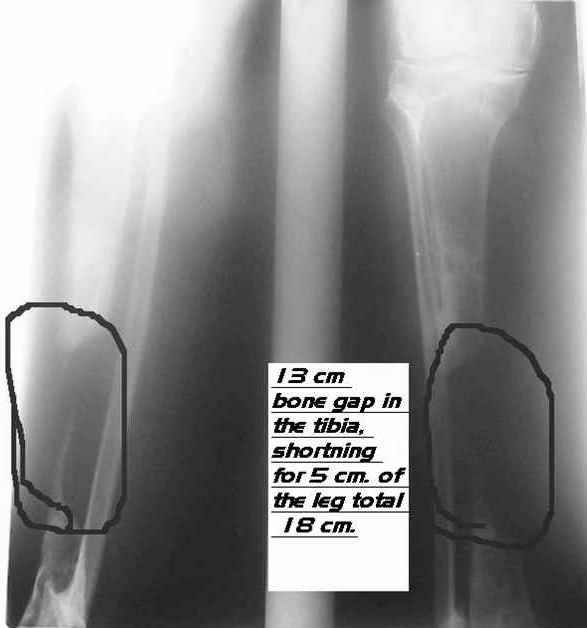

Re: bone defect

Dear Dr. Firas

You can do it like this also...